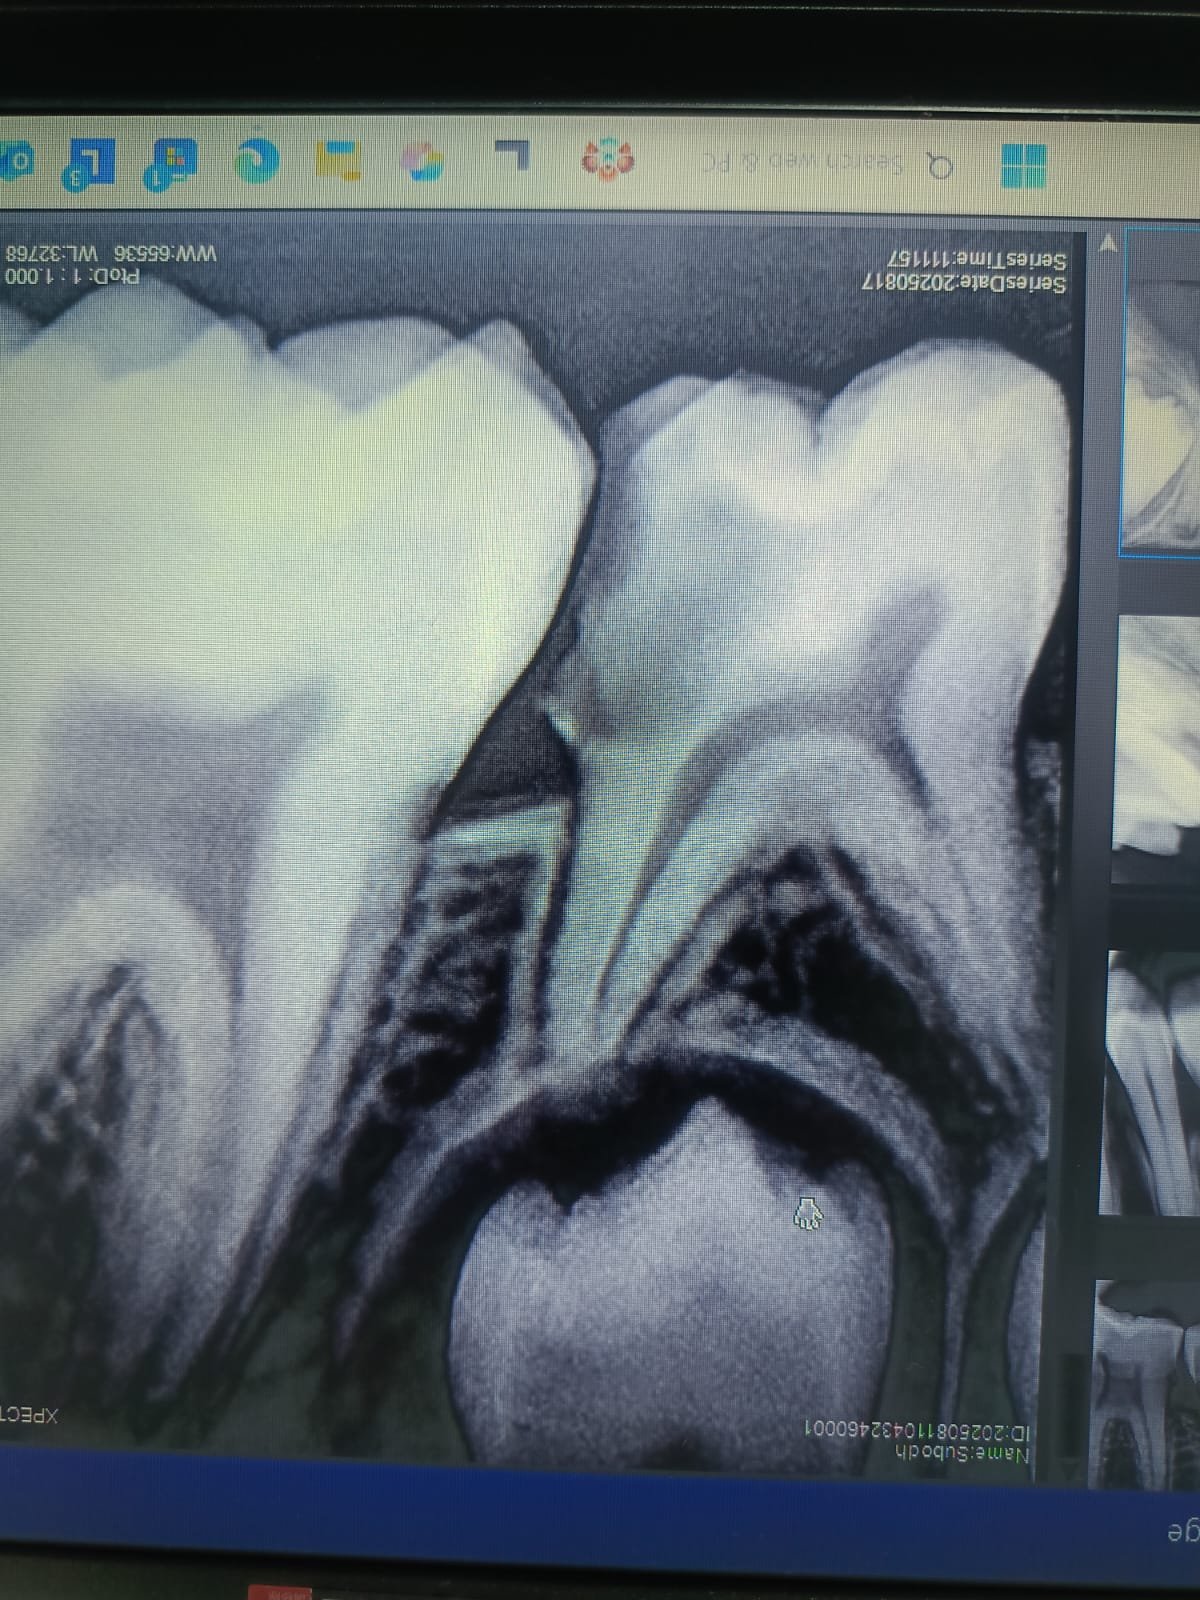

Endodontics (Root Canal)

Endodontics is the specialization focused on the dental pulp and tissues surrounding the root of a tooth. The most common procedure is the Root Canal Treatment (RCT), used to save an infected or damaged tooth.

• Focus: Painless Single-Sitting RCT using modern rotary and microscopic techniques.

• Benefit: Eliminates infection and preserves the natural tooth structure.

Root Canal Treatment Procedure

Clinical Detail: Removal of infected pulp tissue (Pulpectomy).

Extracted Dental Pulp